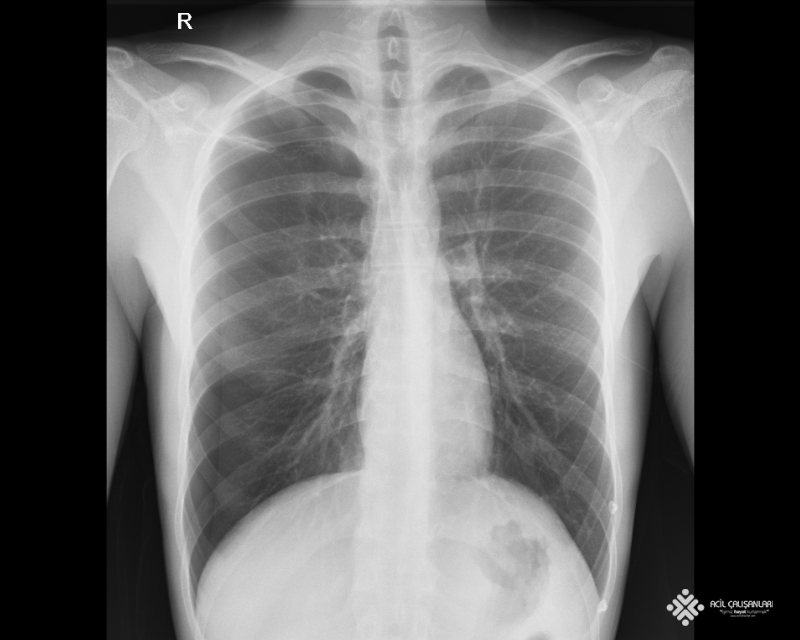

20 yaşında erkek hasta göğüs ağrısı nedeni ile acil servise başvuruyor. Hasta öyküsünde sigara içicisi olduğunu ve birden göğüsünde batma tarzında ğöğüs ağrısı ve merdiven çıkarlen nefes darlığı olduğunu belirtiyor. Hasta yeşil alan doktoru tarafından; GKS'u 15 Nabız: 80 atım/dk düzenli ; Ateşi 36,7 °C ; Solunum sayısı: 14/dk ; SpO2: 98 ; KŞ: 100 ve Kan Basıncı: 140/90 mm/Hg olarak değerlendiriliyor. Fizik muayenede normal olarak değerlendiriliyor. Acil hekimi hastadan aşağıda görülmekte olan akciğer grafisini istiyor. Bu bilgilere göre bundan sonra hastaya uygulanacak en uygun yaklaşım ne olmalıdır?

C) Çekilen ayakta akciğer grafisinde sol hemitoraksta pnömotoraks görünmektedir. Bu yüzden göğüs cerrahisine konsülte edilmeli ve yeşil alanda göğüs cerrahisi gelene kadar beklenmelidir.

D) Çekilen akciğer grafisinde sağ hemitoraksta pnömotoraks görünmektedir. Bu yüzden hasta, spontan pnömotoraks düşünülerek monitörize takip ve tüp torakostomi yapılacak alana çekilmeli ardından göğüs cerrahisine konsülte edilmelidir.

E) Çekilen akciğer grafisinde sol hemitoraksta pnömotoraks görünmektedir. Bu yüzden hasta, spontan pnömotoraks düşünülerek monitörize takip ve tüp torakostomi yapılacak alana çekilmeli ardından göğüs cerrahisine konsülte edilmelidir.